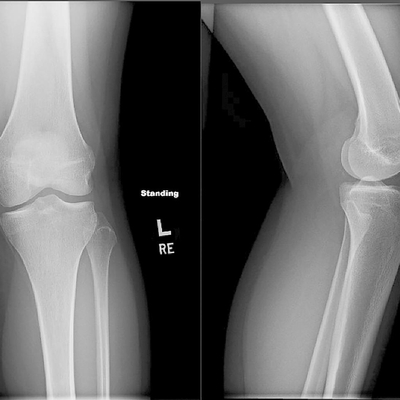

Click on an image below to view more info.